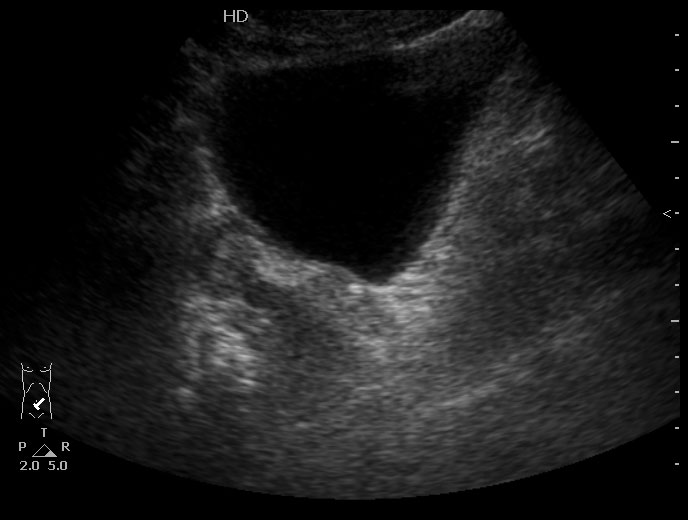

Конкремент в юкставезикальном отделе мочеточника. Пиелонефрит . Субкапсулярный выпот.

Да, МКБ,конкремент юкставезикального отдела мочетоника.

Выпот находится не под капсулой почки, а в периренальном пространстве в самой нижней точке человека прямоходящего.

Особенность этого случая заключается в том,что достаточно выраженные боли не сопровождались расширением ЧЛС, поэтому формула "отсутствие расширения ЧЛС на высоте болей практически исключает уретеролитиаз" здесь оказалась нерабочей.

Проводить инспекцию мочеточника пришлось из-за изменений почки - выпота и повышения эхогенности патенхимы. Как вариант рассматривался тромбоз ПА, но доплерографически он был исключен.

Не видите камня в юкставезикальном отделе мочеточника, предполагаете что это не камень и не в мочеточнике, считаете что это другая патология почки, - что смущает? )

Конкремент в юкставезикальном отделе мочеточника - стрелка.Брехт писал(а):Вокруг камни есть и отёчные стенки мочеточника?; или я допридумываю

Стенки мочеточника без существенных изменений.